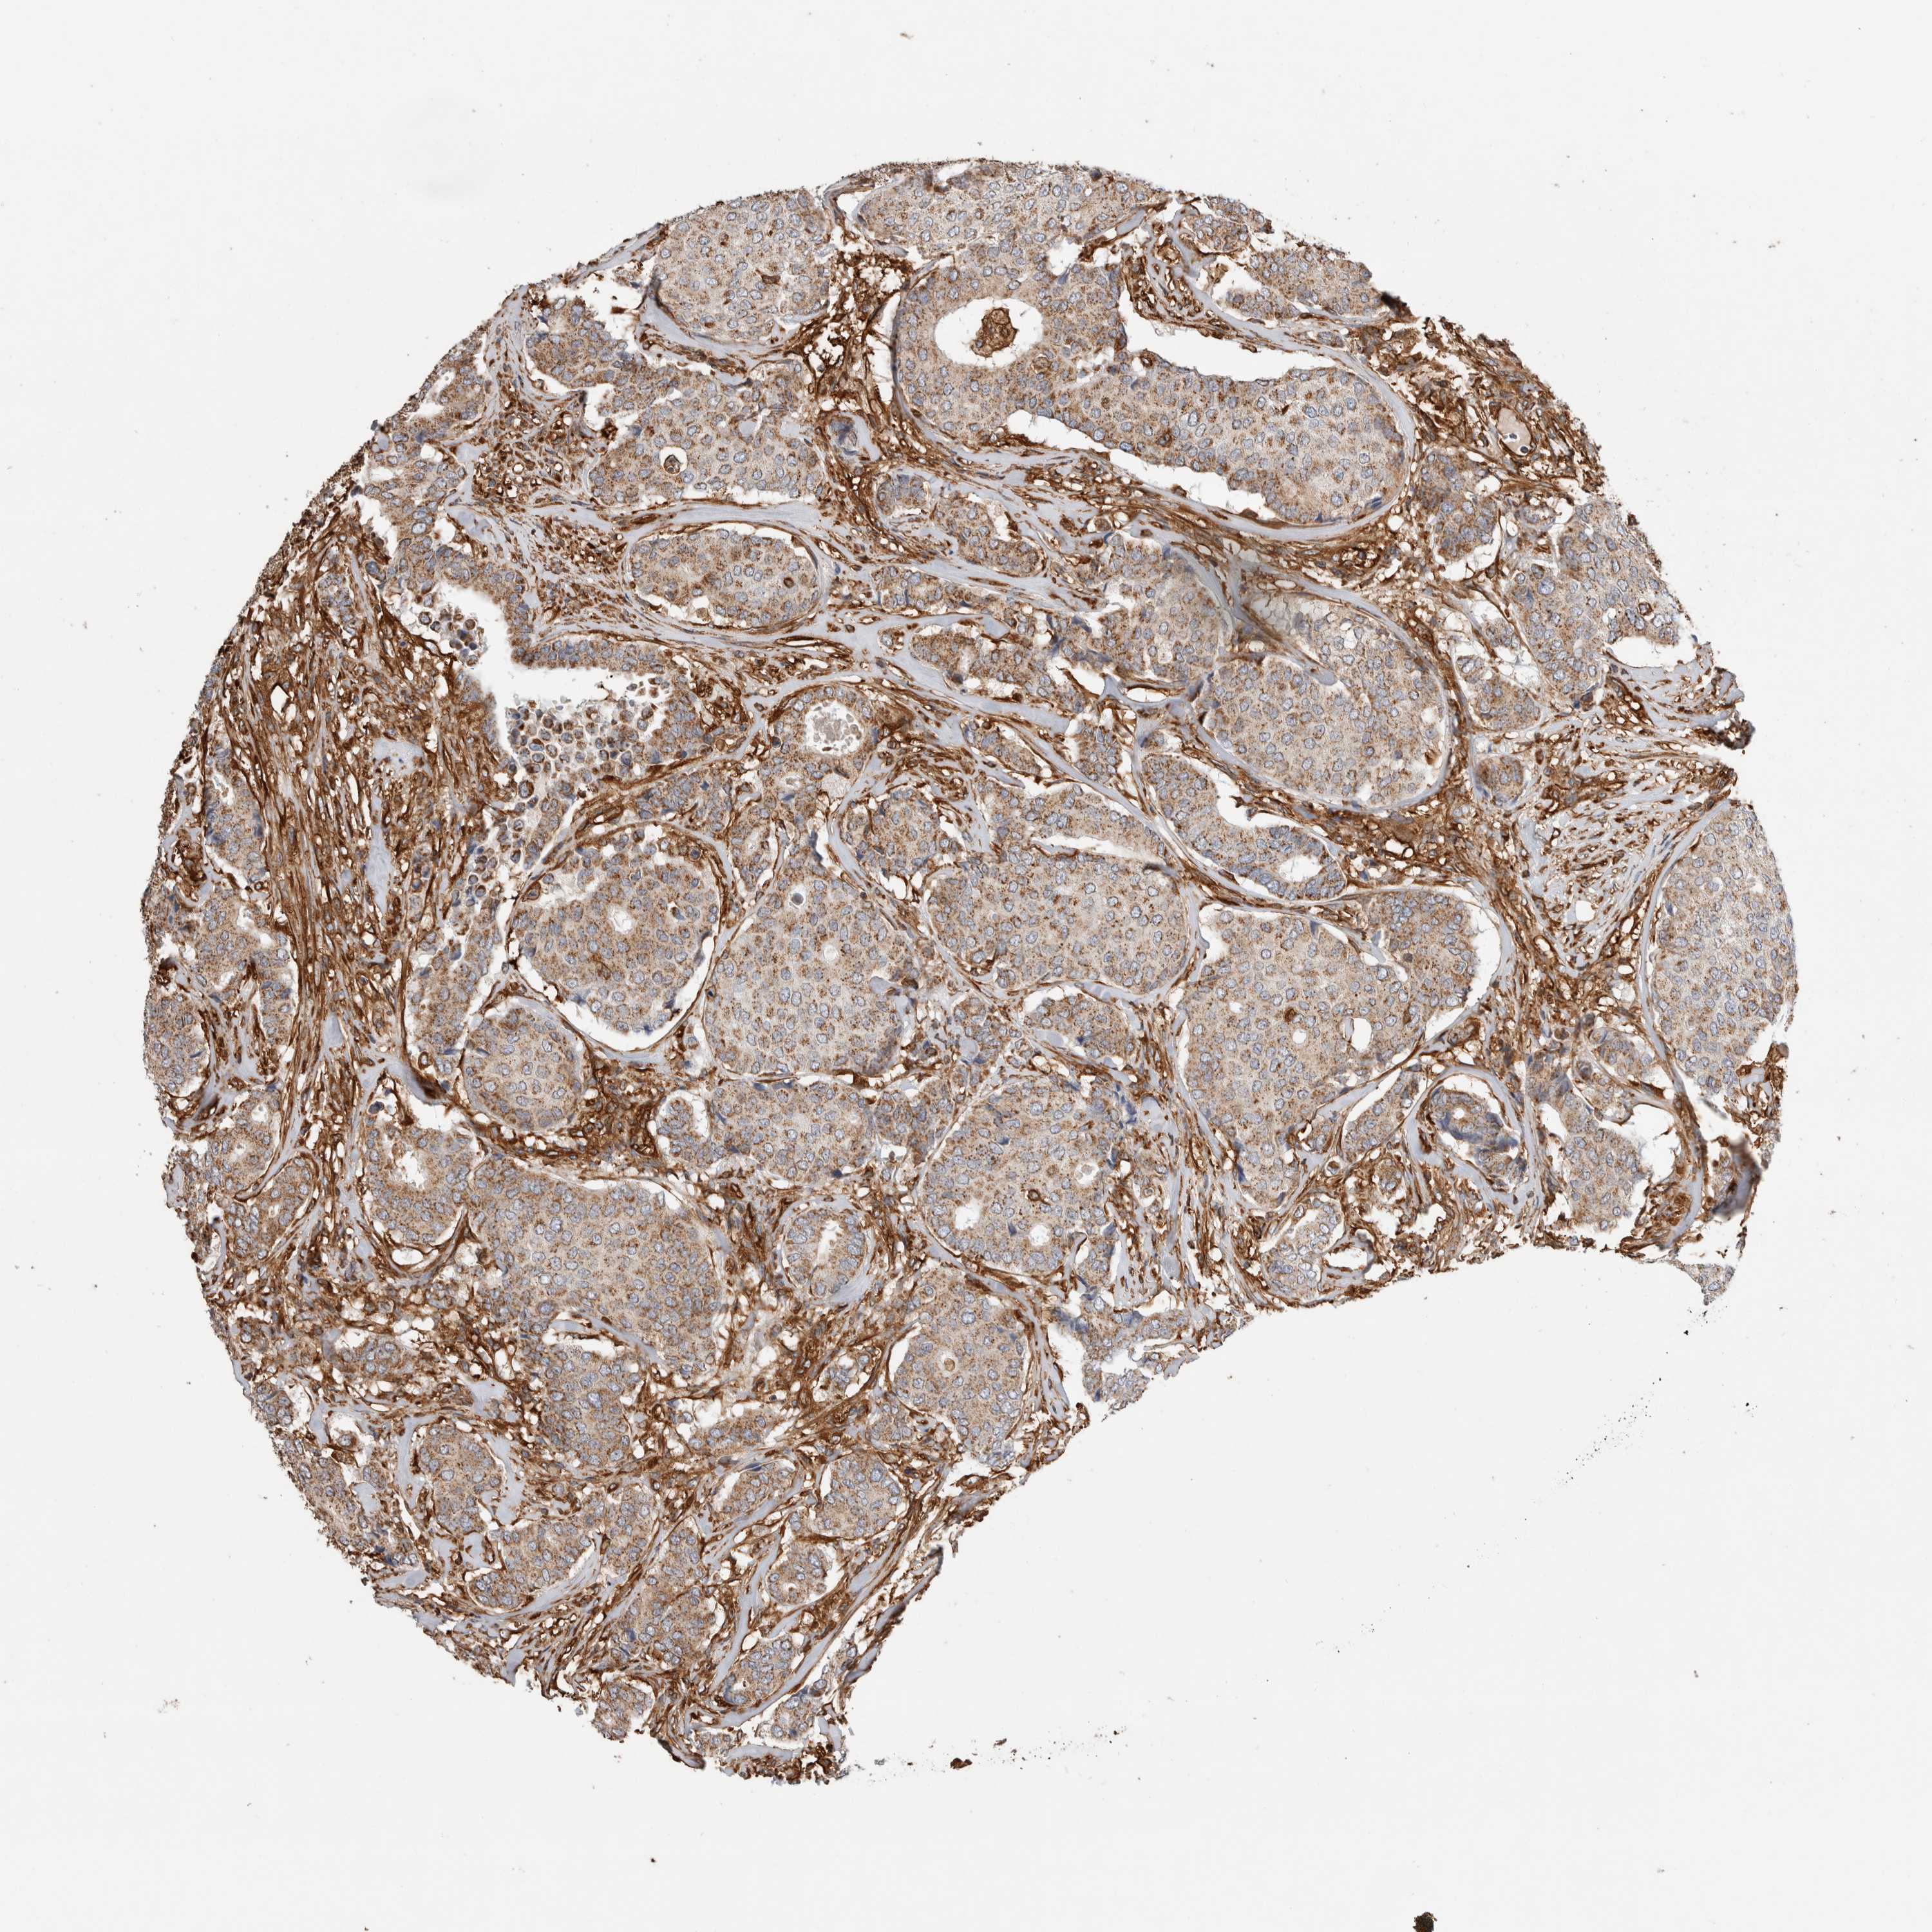

CANCER BREAST CANCER Show tissue menu

BRCA TCGA BRCA VALIDATION PROTEIN EXPRESSION

Breast cancer

Human cancer